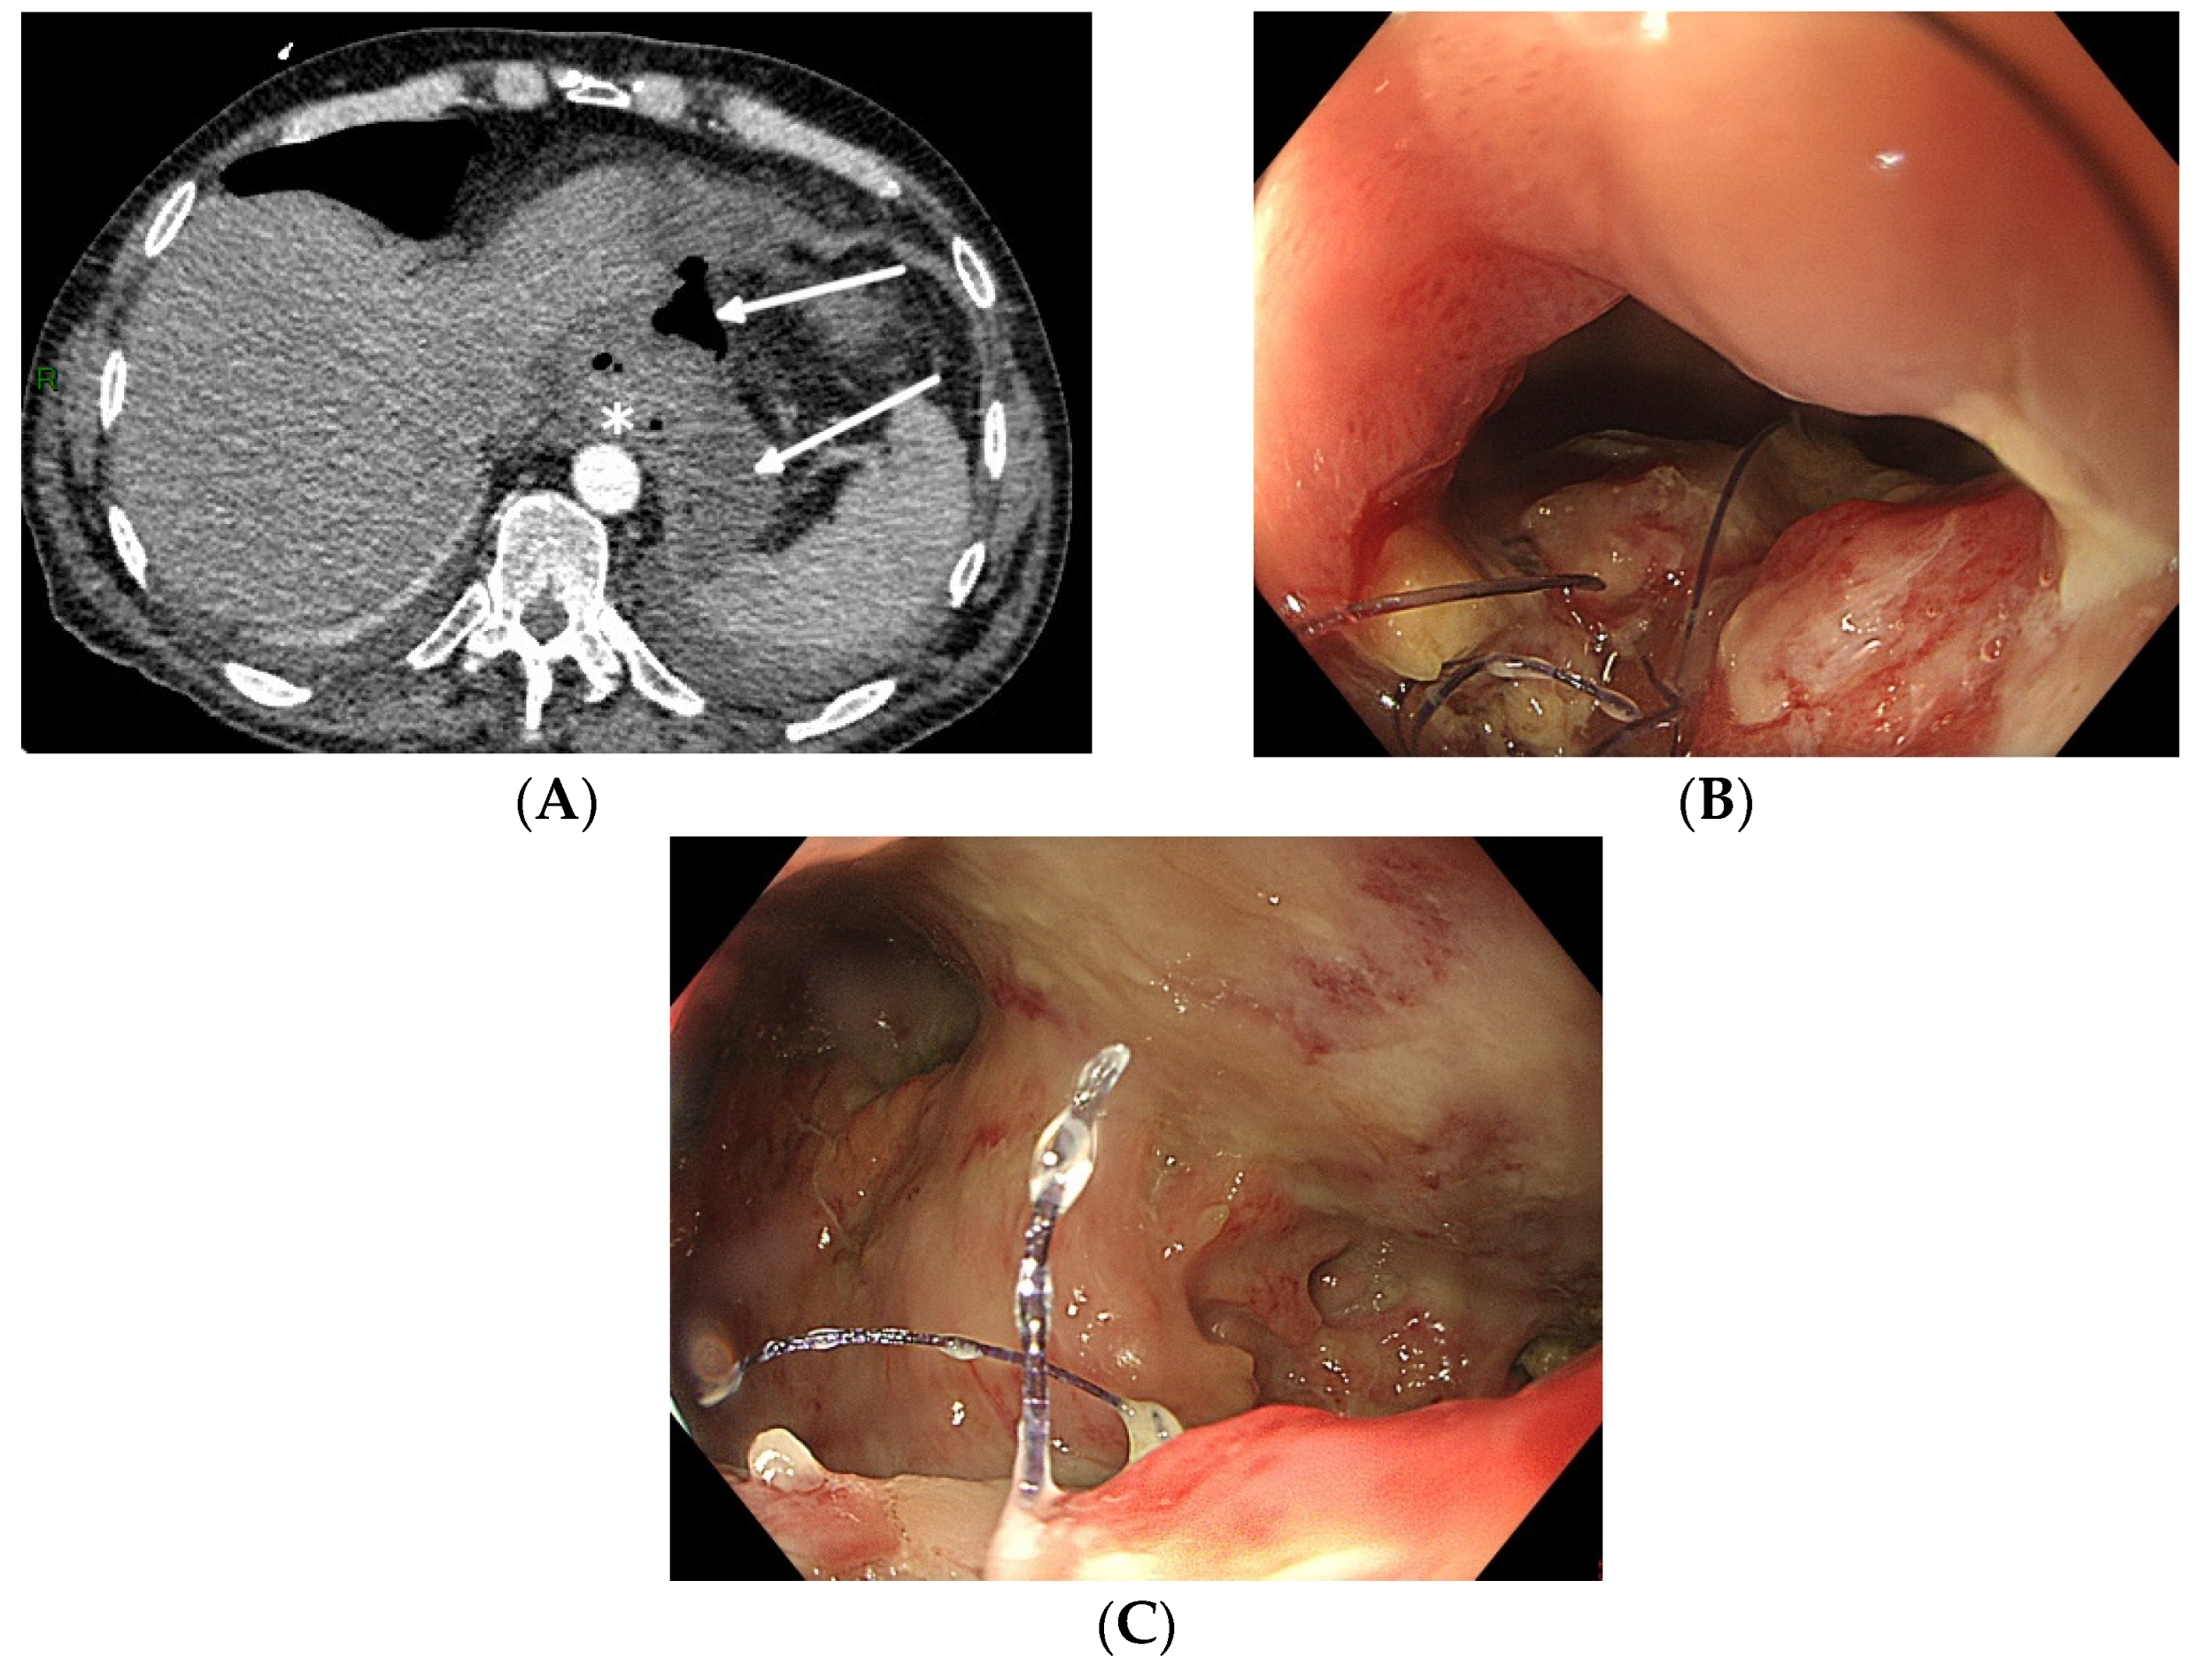

5.1. Pre-Procedure Difficulties

5.2. Intra-Procedure Difficulties

5.3. Post-Procedure Difficulties